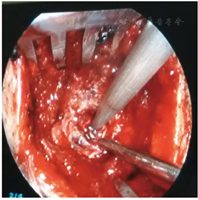

所有患者均在入院后24 h内[4]全麻下行手术治疗。试验组患者术前行头颅CT 1 mm薄扫(图1)、刻盘,并将数据录入神经导航系统;患者全麻取仰卧位,头偏健侧,头架固定并取颅骨标记点进行导航注册,定位手术最佳点,铺单消毒。在患侧颞部切开3~4 cm皮肤切口,充分止血钻孔,切开硬脑膜,通过导航引导组织导管扩张器穿刺至血肿腔内(见封四,图2、图3),取出管芯,将内镜沿组织导管扩张器通道进入血肿腔,由内镜将组织扩张器引导至血肿腔底面,使用吸引器抽吸底面血肿(见封四,图4),直至显露脑组织,向外渐退出组织扩张器,此时见周围血肿回缩至中央,继续抽吸并逐渐退出,依此方式逐渐抽吸血肿至清除完毕,并完全退出扩张器。遇到活动性出血时给予电凝止血,并给予少量明胶海绵覆盖;在创面渗血的地方给予速即沙及少量明胶海绵覆盖。血肿清除完毕后,通过内镜观察残腔无出血及渗血,留置引流管,缝合头皮术毕。